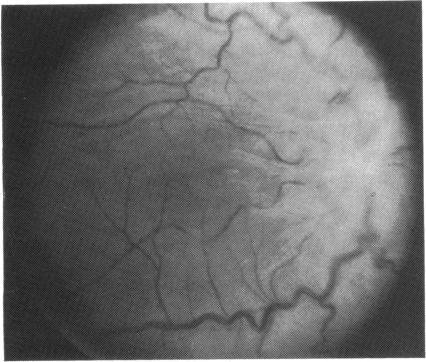

We describe the first case of successfully treated exogenous aspergillus endophthalmitis following penetrating injury and primary scleral wound repair. After repeated vitreous surgery with multiple intravitreous instillations of amphotericin B combined with intravenous antifungal therapy the patient's visual acuity was 6/18. A vigorous approach in the management of mycotic endophthalmitis is emphasised and the role of closed vitrectomy discussed.

我们描述了穿透伤和原发性巩膜伤口修复后成功治疗的首例外源性曲霉性眼内炎病例。在多次玻璃体手术并多次玻璃体内注射两性霉素B联合静脉抗真菌治疗后,患者视力为6/18。强调了在真菌性眼内炎治疗中采取积极措施,并讨论了闭合式玻璃体切除术的作用。